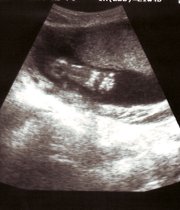

Congreso mexicano promueve ley para comercializar embriones humanos

El proyecto busca ayudar a las parejas que tienen problemas para concebir.